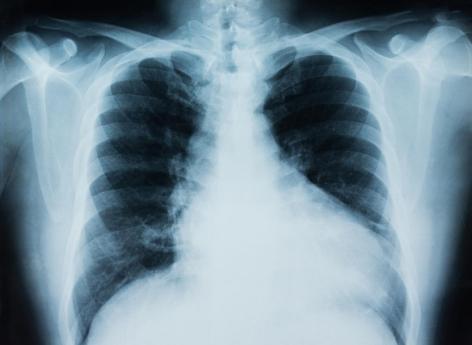

L’étude a porté sur 28 adultes atteints d'un cancer du poumon non à petites cellules (CPNPC) avancé. Des échantillons de sang ont été prélevés avant les traitements, puis à intervalles réguliers par la suite.